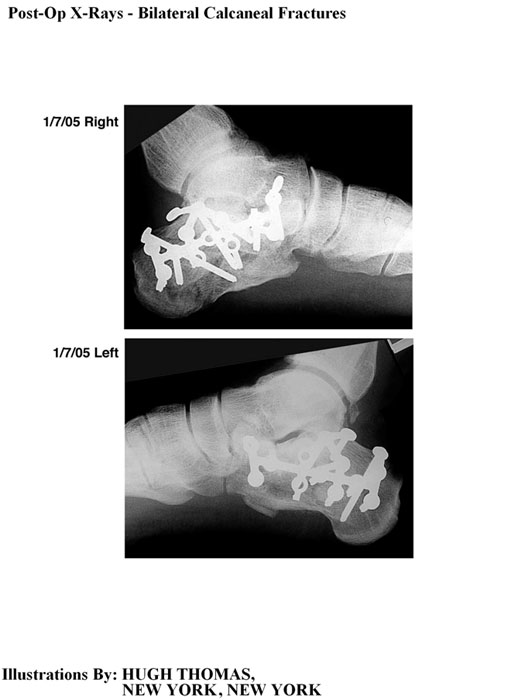

The medical illustrations on this page are examples of the details the attorneys at the Law Offices of William Cafaro prepare for jury presentations.